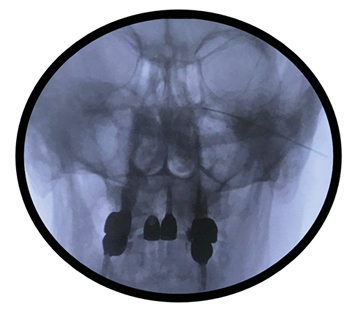

En revisión posterior en consulta, la paciente refirió persistencia de los síntomas asociando una importante incapacidad funcional para la vida diaria y afectación emocional. En vista de la eficacia transitoria de las técnicas realizadas hasta la fecha, la persistencia de restos de tumor en la imagen control y de un examen físico en el que se evidenció gran afectación clínica de la paciente (anestesia para dolor y tacto en territorio de V1 y V2, reflejo corneal ipsilateral abólido, hipoacusia persistente, paresia facial izquierda, hipoestesia para dolor leve en hemicuerpo izquierdo y dolor selectivo sobre cicatriz), se propuso realizar radiofrecuencia pulsada del ganglio esfenopalatino izquierdo mediante abordaje infracigomático (Figura 2). Esta técnica se realizó sin incidencias, obteniéndose un alivio más duradero que la técnica transnasal, por lo que en el seguimiento de la paciente en consulta insistimos en avanzar con la radiofrecuencia térmica en una siguiente sesión.

Fig. 2. Fluoroscopia en proyección anteroposterior de abor-daje infracigomático del ganglio esfenopalatino.